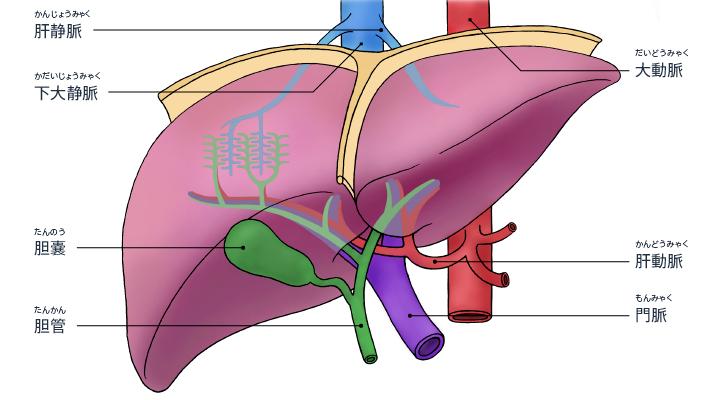

胆道系统组成:由肝内胆管、肝外胆管、胆囊及 Oddi 括约肌组成。

胆囊:分为底、体、颈三部,为囊性器官,呈梨形,位于肝脏脏面的胆囊窝内,相当于肝右叶与肝方叶之间。长 8~12 cm,宽 3~5 cm;容积 40~60 ml。胆囊管、肝总管及肝脏脏面三者构成的三角形区域称为胆囊三角 (又叫 Calot 三角、卡洛氏三角 Calot's triangle、hepatobiliary triangle 、胆囊动脉三角)

胆囊管:是连接胆囊与胆总管之间的管道,一般长约 2.5~4 cm,管径约 0.2~0.3 cm。胆囊管具有多种的解剖学变异。

肝总管:左、右肝管出肝后,在肝门部汇合形成肝总管。肝总管直径为 0.4~0.6 cm,长约 2~4 cm,位于肝十二指肠韧带中,其下端与胆囊管汇合形成胆总管。

胆总管:由肝总管与胆囊管在肝十二指肠韧带中汇合形成,全长约 7~9 cm,直径 0 .6~0 .8 cm,直径一般不超过 1 cm。分为四段:十二指肠上段、十二指肠后段、胰腺段、十二指肠壁内段。

大多数人胆总管与主胰管在肠壁内汇合形成一共同通道,并膨大形成胆胰壶腹。另有 15%~20% 的胆总管与主胰管分别开口于十二指肠。Oddi 括约肌主要包括胆管括约肌、胰管括约肌和壶腹括约肌,它具有控制和调节胆总管和胰管的排放,以及防止十二指肠内容物反流的重要作用。

正常肝内的胆管与肝动脉及门静脉的肝内分支相互伴行,肝右叶右前、后叶肝管在肝门静脉右支前上方汇合组成右肝管,肝左叶左外上、下段肝管于肝门静脉左支横部的前上方汇合构成左肝管,肝总管下行于肝十二指肠韧带内,在韧带内胆囊管与肝总管以锐角汇合形成胆总管,与十二指肠大乳头处胆总管与主胰管汇入肠管内。肝内胆管主要对由肝细胞产生的胆汁起到输送作用,胆囊管是连接胆囊与肝外胆管的重要结构,胆总管主要是确保胆汁可以由胆囊腔进入肠道内。